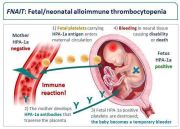

| 14:41, 18 באפריל 2024 | FNAIT 2.png (קובץ) |  |

67 קילו־בייטים | Motyk | 1 | |

| 14:36, 18 באפריל 2024 | FNAIT1.jpg (קובץ) |  |

59 קילו־בייטים | Motyk | 1 | |